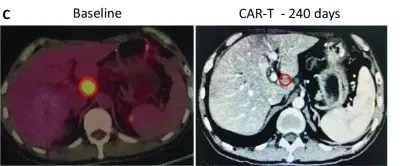

更绝的是1例晚期胰腺癌患者,接受的是静脉回输的CAR-T治疗,治疗后全身的病灶,基本都实现了代谢活性完全消失。

在治疗240天后达到完全缓解,未见其他肿大的淋巴结,患者病灶完全消失